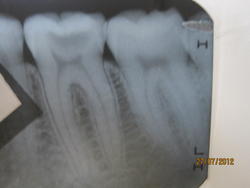

здравствуйте! с октября 2011 года начал болеть зуб. боль ноющая, проходит со временем. зуб чувствителен к холодному и горячему, иногда как бы "стреляет" при жевании, иногда болит даже без перечисленных без причин. замечала иногда неприятный запах или привкус от этого зуба при жевании. в последние 2-3 дня боль стала еще сильней, есть или пить страшно. на любое изменение температуры зуб отдает ужасной болью. с виду здоров, по словам стоматолога кариозных плоскостей нет (хотя есть несколько маленьких черных точек), десны тоже здоровые. сделала снимок, стоматолог (платный) сказал, что пятно на снимке в верхней части зуба - это вторая камера (очень редкое явление) и что не видит причин для того, чтобы его "ковырять". что вы можете сказать судя по снимку зуба? интересует тот, что слева. что может быть причиной таких болей? есть ли смысл удалять нерв, например, или можно вылечить зуб без вмешательства? и вообще, что можно с этим сделать?